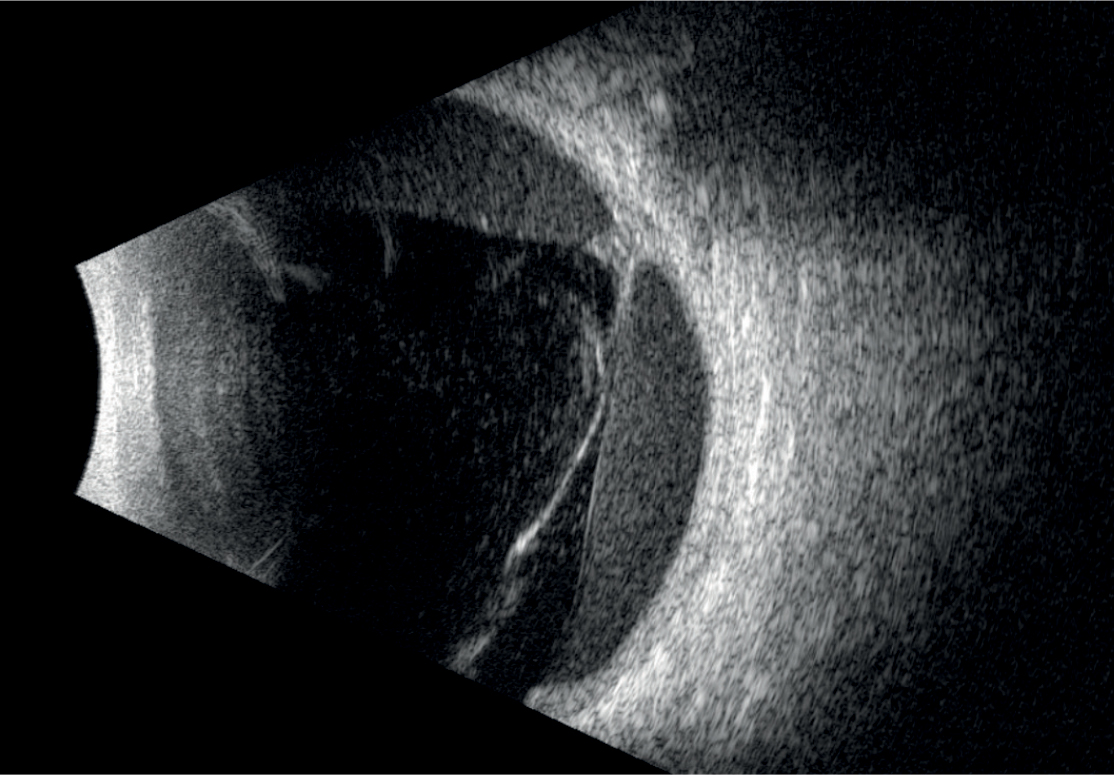

ABSolu prichádza s novým typom 20 Mhz B-sondy, pozostávajúcej z piatich snímačov rôznych priemerov, ktorá zvyšuje hĺbku poľa o 70% a laterálne rozlíšenie o 27%. To umožňuje simultánne vyšetriť patológie sklovca, sietnice a orbity bez ústupkov na kvalite snímky. Štandardizovaná sonda zas zabezpečuje diagnostiku tumorov, odlúpenia sietnice, či Gravesovej choroby. Sondy B15 a B20 obsahujú senzor, ktorý automaticky zisťuje a v reálnom čase znázorňuje polohu sondy a smer lúča.

- väčšia hĺbka ostrosti umožňujúca vizualizáciu celého oka,

- vynikajúce rozlíšenie od prednej časti sklovca až k stenu,

- zobrazovacia technológia UBM s rôznymi zobrazovacími režimami,